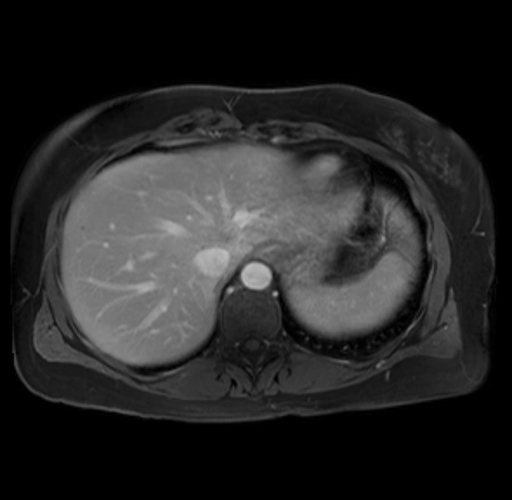

Imaging Analysis

Look through the patient's CT scan to identify any areas of concern for the necessary procedure.

Based on your CT findings, which issue(s) are present and would give reason for "planned slowing down moment(s)" in this case?

Considering a standard distal pancreatectomy procedure, what step(s) of the operation would you do differently in this case?